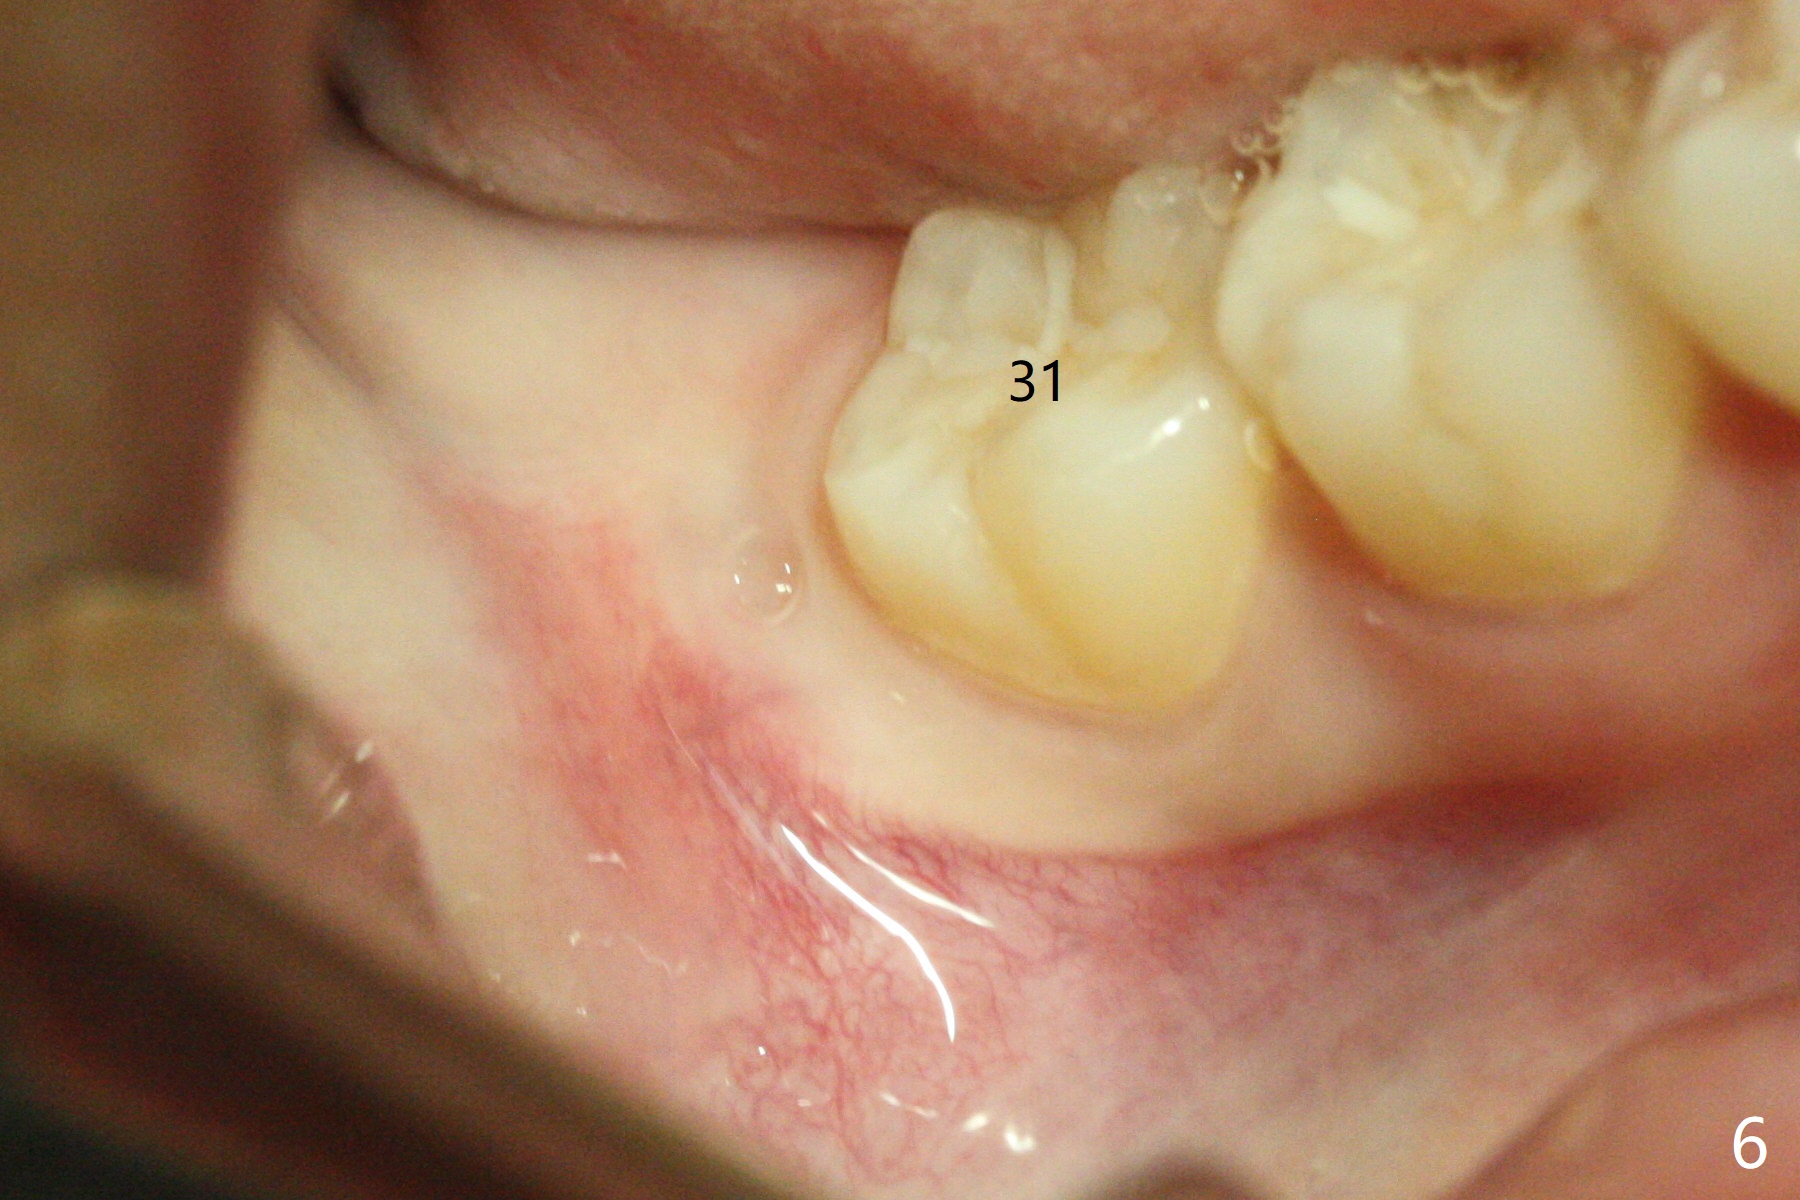

A 25-year-old woman, under our care for the last 11 years (Fig.1-6), returns for #1 and 32 extraction (1 year after #16 and 17 extraction (Osteogen plug)). Preop PA shows that a portion of the lower impacted tooth may be located buccal to the tooth #31 (Fig.4 black dashed line). An accessory incision is moved from distobuccal to midbuccal (Fig.7 arrowheads) to reduce postop loss of bone graft (Fig.8 B) from the incision. In fact the incision should be further moved to mesiobuccal (Fig.9 red line) if buccal impaction is suspected (curved black line). The buccal impaction of #32 of her father is more severe.